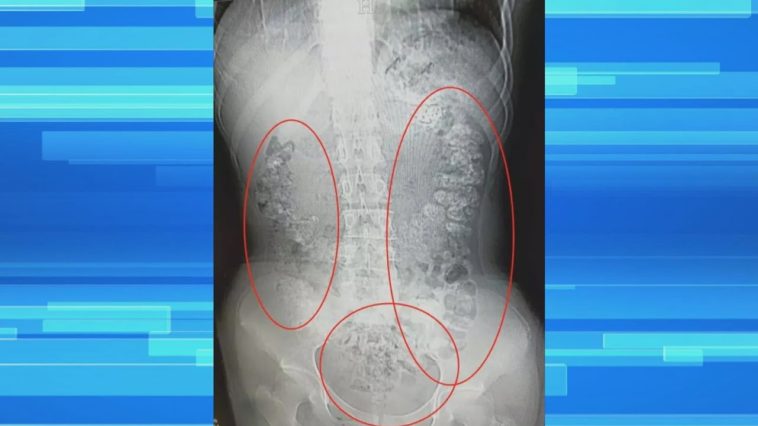

Doctors Say Large Amounts Of Tapioca Starch Can Be Hard To Digest. SACRAMENTO (CBS13) — Can you have too much boba? For one 14-year-old in China, the answer is yes. She had to be hospitalized after more than 100 tapioca balls were found stuck in her stomach.